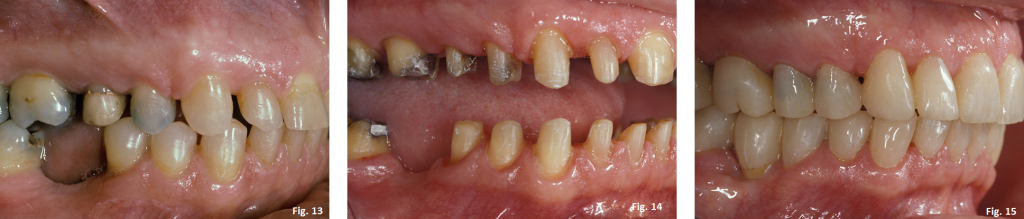

Taking this “additional” step to create the occlusal plane guide is a great way to help assure that the provisional restorations are created in the correct plane of space anterio-posteriorly and mesio-distally. (Figs. 13-15)